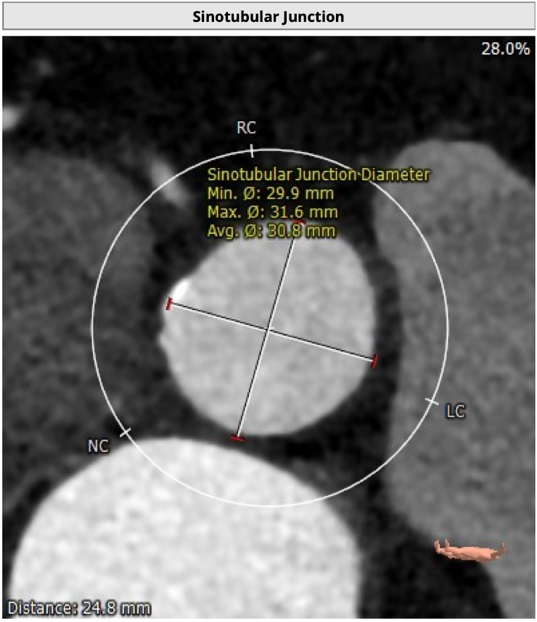

主动脉根部评估

CT 数据显示该患者为二叶式主动脉瓣

STJ 短径29.9mm,长径31.6mm;